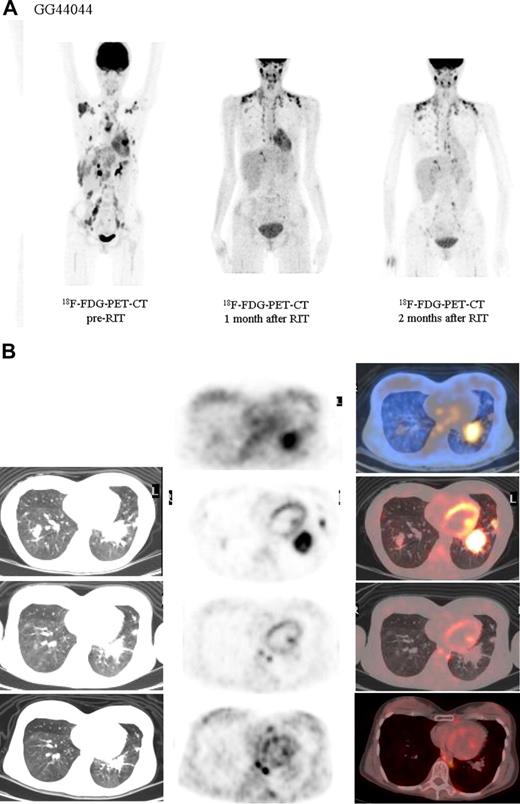

Both HL patients also showed favorable lesion/bone marrow dosimetry estimates after receiving diagnostic 131I-L19SIP, with an absorbed dose of radioactivity to the target lesions—a pulmonary lymphoma lesion (patient HL1) and a left basal pulmonary lesion and a right axillar lymphoma conglomerate (patient HL2)—estimated to be approximately 14 and 22.7 Gy, respectively. The absorbed dose to the red bone marrow was calculated to be 1.3 and 0.85 Gy for HL patients HL1 and HL2, respectively. In HL patient HL1, the SPECT-CT images acquired 12 days after a dose of 5.55 GBq 131I-L19SIP demonstrated selective ED-B FN targeting in multiple parenchymal lung lesions and in enlarged supraclavicular and lumboaortic lymph nodes with all such sites corresponding to high 18F-FDG uptake on baseline PET-CT scans (Figure 6). In the second HL patient (HL2), the SPECT-CT images acquired 12 days after a dose of 3.7 GBq 131I-L19SIP demonstrated selective ED-B FN targeting in multiple enlarged axillar and supraclavicular (both sides), paratracheal, subcarinal, pleural, as well as peritoneal and iliacal (both sides) lymph nodes. ED-B FN–expressing lymphoma lesions were also found in the right and left basal lobes of the lung. All ED-B FN–expressing lymphoma lesions corresponded to high 18F-FDG uptake on baseline PET-CT scans (Figure 7). Both HL patients experienced a partial clinical response according to RESCIST criteria at 1 month after therapy with shrinkage of the sum of diameters of the measurable lymphoma lesions of 44% (134 to 75 mm; baseline to 1 month after treatment) and 39% (417 to 256 mm) for patients HL1 and HL2, respectively. This partial response was confirmed at 2 and 3 months after 131I-L19SIP therapy for both HL patients. The 3 lymphoma patients did not experience any acute toxicity during or after 131I-L19SIP therapy. Mild and transient thrombocytopenia was observed in both HL patients, but not in the SLL NHL patient, with a nadir of 22 and 52 × 109 platelets/L for patients HL1 and HL2, respectively, at 6 weeks after 131I-L19SIP injection.

Objective partial remission in another advanced Hodgkin lymphoma patient (HL2) induced by 131I-L19SIP radioimmunotherapy. (A) 18F-FDG PET scans show intense glucose metabolism in multiple enlarged lymph nodes, particularly in right and left axillary and supraclavicular nodes, in paratracheal, subcarinal, peritoneal, and iliacal nodes as well as in lymphoma lesions located in the basal lobes of both lungs (leftmost image). One (center) and 2 (rightmost image) months after application of therapeutic 131I-L19SIP (3.7 GBq), the number and size of active lymphoma lesions decreased substantially. (B) 18F-FDG PET scans and 131I-L19SIP SPECT-CT images from the same patient. Transaxial SPECT-CT images (top row) show selective 131I-L19SIP uptake to a pulmonary lymphoma lesion still detectable 12 days after injecting a therapeutic dose (3.7 GBq). Transaxial 18F-FDG PET scans captured prior to (second row), 1 month after (third row) and 2 months after (bottommost row) application of therapeutic 131I-L19SIP show a significant shrinkage in size and a complete disappearance of metabolic activity in the initially large pulmonary lymphoma lesion, indicative of lymphoma response to 131I-L19SIP radioimmunotherapy.